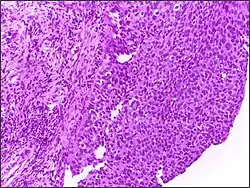

Squamous cell carcinoma of cervix | Invasive Squamous Carcinoma of the Cervix. Cold Knife Cone. | Category: Histopathology of squamous cell carcinoma of the cervix | Invasive squamous carcinoma of cervix |

![]() |